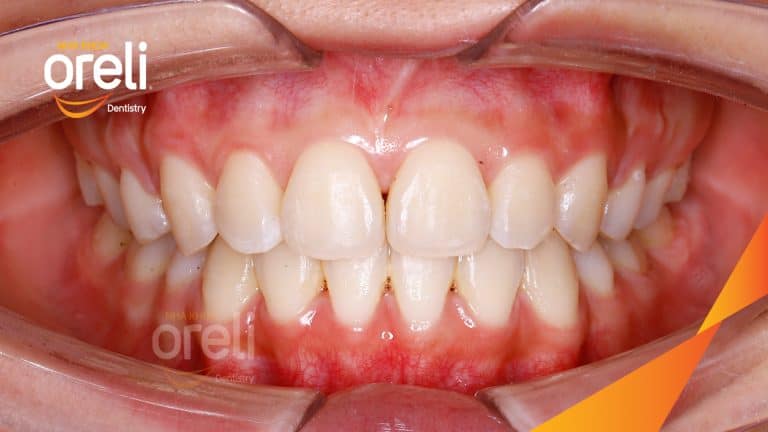

Ca niềng chỉnh chen chúc sai khớp cắn hạng 3 móm nhẹ – Kết quả thực tế ở Oreli Niềng răngChen chúcMóm Xem thêm